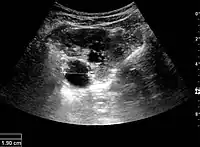

Complex cysts can have membranes dividing the fluid-filled center with internal echoes, calcifications or irregular thickened walls. The complex cyst can be further evaluated with Doppler US, and for Bosniak classification and follow-up of complex cysts, either contrast-enhanced ultrasound (CEUS) or contrast CT is used (Figure 6). The Bosniak classification is divided into four groups going from I, corresponding to a simple cyst, to IV, corresponding to a cyst with solid parts and an 85–100% risk of malignancy.[1] In polycystic kidney disease, multiple cysts of varying size in close contact with each other are seen filling virtually the entire renal region. In advanced stages of this disease, the kidneys are enlarged with a lack of corticomedullary differentiation (Figure 7).[1]